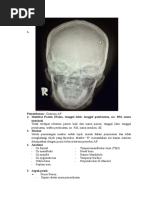

Radiographic Critique Form (RCF)

Examination = Mandibula PA Ya/Tidak Diskripsikan hasil analisis

Persyaratan identifikasi Tidak Tidakterdapat ID pasien

Penempatan marker dengan benar Ya Terdapat marker R, penempatansudahbenar

Gambaran anatomi dalam radiograf? Ya Keseluruhanbagian mandibular termasuk ramus,

dan body mandibular

terproyeksidantidakterpotong.

Apakah gambaran anatomi tampak sesuai Ya Kedua condyles mandibular

dengan proyeksi ini? danangulusmadibulaterproyeksidenganjelas.

Apakah kolimasi lapangan radiasi cukup? Ya Tampakkolimasiatauluaslapanganpenyinaransesu

Dan tetap mengindahkan ALARA (limitasi, aidenganobjek yang terperiksa

justifikasi, optimasi)?

Proteksi radiasi, presentasi, menghalangi Tidak Tidakterdapatalatproteksiradiasiygmengganggura

gambaranobyek? diograf.

Garis tepi luar kortek tulang, patren trabekula Ya Untuktepiluarkortektulangdantrabekulaterlihat,

tulang, dan atau struktur soft tissue terlihat soft tissue terlihat.

tajam?

Radiograf terlihat tanpa distorsi? Ya Tidakterlihatkekaburangambaranradiograf

Ukuran film benar, regio organ anatomi Ya Ukuran film yang digunakansesuai,

terlihat sesuai dan benar? penempatankasetsudahbenar

Menggunakan alat penerima gambar yang Ya Ukurankasetdan film yang digunakansesuai

sesuai?

Kecukupan daya penetrasi sinar dengan Ya Faktorekspositepatdapatmenampakkanmandibula

kerapatan? denganjelas

Kecukupan kontras gambar? Ya Faktoreksposi yang

digunakancukupdlmmenampakkan mandibular

sehinggamandibulaterlihatdalamradiograf

Upaya pencegahan terhadap artefak gambar? Ya Tidakterlihatartefakradiograf yang

dapatmenganggudiagnosa

Outcome yang dikehendaki (contoh; Tidak Gambarananatomimandibulatampakdalamproyek

pemakaian sinar-xdapat memperlihatkan nilai si. Gambaranmandibula juga

diagnostik dari regio organ anatomi)? terlihatjelassehinggamembantudalammenegakka

n diagnose (kemungkinanfrakturpadaangulus

mandibular)

Kesimpulan Radiograf ini adalah :

DITERIMA/ACCEPTED TIDAK

DITOLAK/REJECTED Ya Anatomisesuai dg proyeksi yang

dimintanamunsuaturadiografharusdiberi ID

pasien agar

radiograftidaktertukardenganradiografpasien lain

sehinggatertukarnya diagnose tidakakanterjadi.

Jika ditolak/rejected apa upaya yang Diberikan ID pasien.

sebaiknya dilakukan dengan cara yang

berbeda untuk memperbaikiketidaksesuaian

teknik yang telah dilakukan